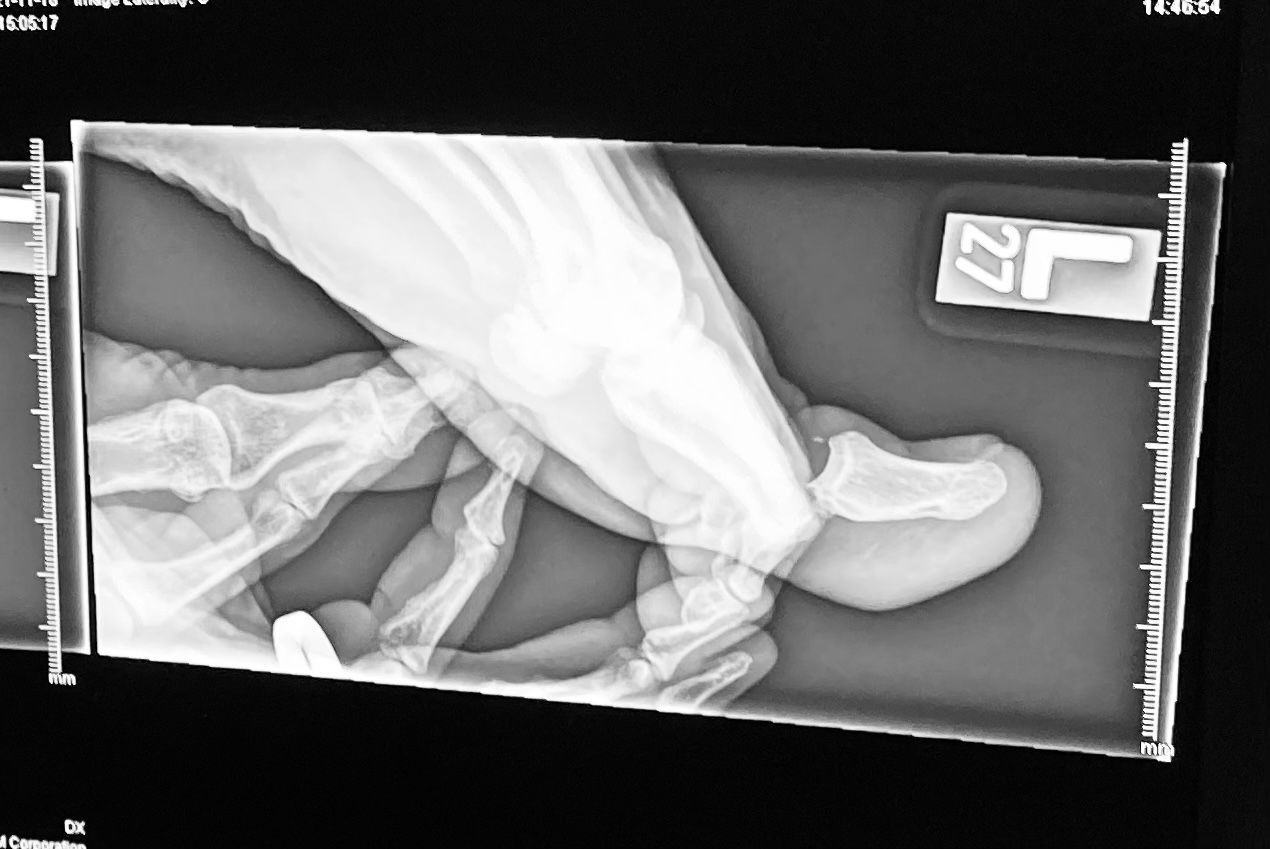

We went to the ER where they did an X-ray and I found out that it’s not broken, just dislocated. The doctor gave me some local anesthetic and pulled the toe until it popped back in. I've had better times, but it's all good now as the toe is in its normal position.